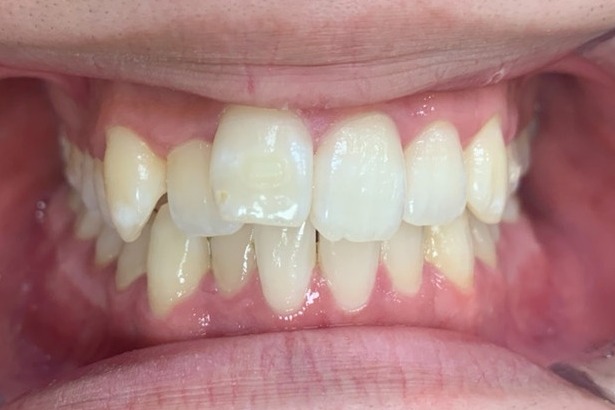

人と接する機会が多く、第一印象を大切にしたいと考え、写真写りや笑顔への自信を高めたいという思いから矯正を決意された矯正当時学生だった22歳男性の H.S.様に、スマイルモア矯正を選んだ理由を伺いました。

| 費用 | 360,000円(税込396,000円) |

| 治療期間 | 11ヶ月 |

| 治療内容 | マウスピースを用いた歯列矯正 |

| 追加処置 | IPR |

以前よりも歯並びが改善され、人とコミュニケーションをとることに自信がつきました。 「スマイルモア」という名前の通り、笑顔に自信がついたことで今までよりも口を開けて笑う機会も増えました。 矯正期間が年単位だったのですぐに変化があったわけではないですが、綺麗な仕上がりに満足しています。